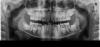

Sanvean Опубликовано 14 августа, 2013 Поделиться Опубликовано 14 августа, 2013 Здравствуйте! Мальчик, 11 лет. Основная жалоба -- неровный зубной ряд: 11 и 21 расположены глубже 12 и 22. Показались ортодонту, он рекомендовал удалить все молочные зубы (правда, снимка он не видел) и уже потом решать вопрос с установкой пластинки. Стоит ли торопится удалять зубы или можно подождать, пока они не выпадут самостоятельно?Спасибо. Ссылка на комментарий

Ayrat_zub Опубликовано 14 августа, 2013 Поделиться Опубликовано 14 августа, 2013 Здравствуйте! Мальчик, 11 лет. Основная жалоба -- неровный зубной ряд: 11 и 21 расположены глубже 12 и 22. Показались ортодонту, он рекомендовал удалить все молочные зубы (правда, снимка он не видел) и уже потом решать вопрос с установкой пластинки. Стоит ли торопится удалять зубы или можно подождать, пока они не выпадут самостоятельно?post-16614-0-67958600-1376466121.jpgСпасибо. фото бы еще) есть такая философия,Марсел Корн если правильно помню читал, если места действительно для постоянных зубов недостаточно, то после удаления оставшихся молчных зубов, устанавливаются накусочныые площадки, и губные бампера, может ваш ортодонт что-то подобное хочет провернуть. хотя без фото не берусь точно говорить) Ссылка на комментарий

Sanvean Опубликовано 15 августа, 2013 Автор Поделиться Опубликовано 15 августа, 2013 Фото Ссылка на комментарий

Ayrat_zub Опубликовано 5 ноября, 2013 Поделиться Опубликовано 5 ноября, 2013 (изменено) Фотоs1.JPGs2.JPGтак, тогда еще и ТРГ обязательно)) если будет с расчетом снимка вообще идеально) и фото не передних зубов, а полностью зубных рядов) Изменено 5 ноября, 2013 пользователем Ayrat_zub Ссылка на комментарий